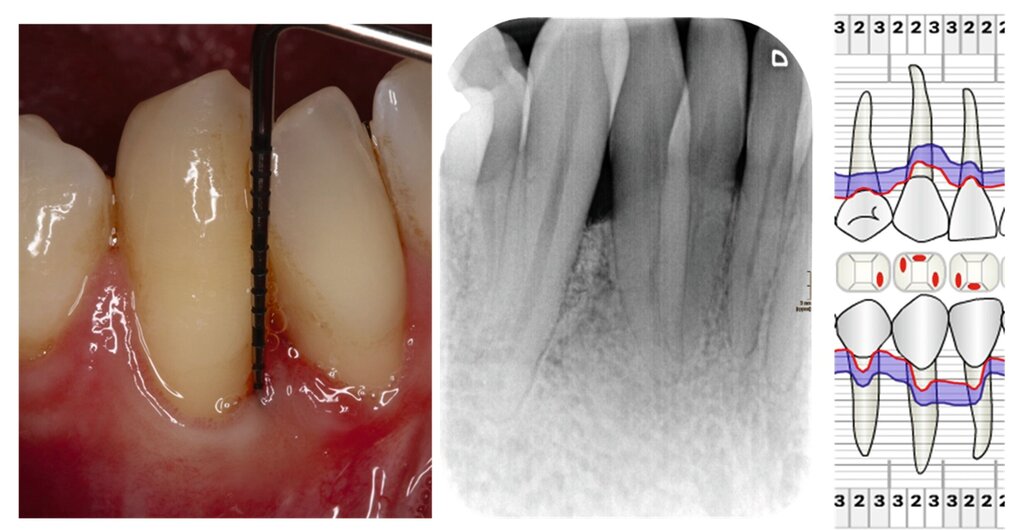

Die parodontale Regeneration ist eine gute Therapiemöglichkeit, um die Prognose von stark betroffenen Zähnen mit tiefen Resttaschen und Knochendefekten oder Furkationsdefekten zu verbessern. Der zusätzliche Nutzen für den Attachmentgewinn liegt bei durchschnittlich 1,34 mm und für die Reduktion der Sondierungstiefen bei 1,2 mm [Nibali et al., 2020]. Eine gute Plaquekontrolle wirkt sich dabei positiv auf das Heilungsergebnis aus und sollte deshalb die Basis für alle parodontalchirurgischen Maßnahmen sein [Rosling et al., 1976]. Auch Zähne mit Furkationsbefall sollten in die Parodontaltherapie einbezogen werden. Bei Furkationen von Unterkiefermolaren Grad II und Oberkiefermolaren mit bukkalem Furkationsbefund Grad II sollten regenerative parodontalchirurgische Maßnahmen in Betracht gezogen werden [Jepsen et al., 2020]. Zur Unterstützung der Regeneration von Knochentaschen oder Furkationsbefall Grad II stehen gut untersuchte Biomaterialien wie Membranen oder Schmelz-Matrix-Proteine mit oder ohne Zusatz von Knochenersatzmaterial zur Verfügung [Nibali et al., 2020]. Die Abbildungen 1 bis 3 zeigen einen Fall, bei dem durch eine regenerative Parodontalchirurgie die Prognose des Zahnes maßgeblich verbessert wurde.

Mehrere Studien berichten über gute Langzeitergebnisse nach dieser Therapieform, insbesondere auch bei primär „hoffnungslos“ eingestuften Zähnen [Cortellini und Tonetti, 2004; Pretzl et al., 2009; Nygaard-Østby et al, 2010; Cortellini et al., 2020; Sculean et al., 2008]. In einer Studie von Cortellini et al. [2020] wurden 50 Patienten mit je einem „hoffnungslos“ prognostizierten Zahn (Knochenabbau ad apex) entweder der Testgruppe (regenerative Behandlung) oder der Kontrollgruppe (Extraktion mit Implantation durch festsitzenden Zahnersatz) zugeteilt. Die Überlebensraten nach zehn Jahren betrugen 88 Prozent für die Test- und 100 Prozent für die Kontrollgruppe. Die Kosten der Therapie waren in der Testgruppe signifikant geringer. Auch wenn die Ergebnisse beeindrucken, ist kritisch anzumerken, dass alle Patienten im Zeitraum von zehn Jahren vierteljährliche Recall-Sitzungen erhielten und die Therapie in einer hoch spezialisierten Praxis durchgeführt wurde. Das heißt, dass diese techniksensitive Therapie in einer allgemeinzahnärztlichen Praxis nicht unbedingt den gleichen Erfolg erzielen würde. Dennoch zeigt die Studie, dass auch bei schwer erkrankten Zähnen noch Regenerationspotenzial besteht und man sich auf die erste prognostische Einschätzung nicht einhundertprozentig verlassen kann. Auch mit nicht-chirurgischer Parodontitistherapie und konsequenter Erhaltungstherapie konnten in einer weiteren Studie 88,2 Prozent der primär als fraglich und 59,5 Prozent der primär als hoffnungslos eingestuften Zähne über einen Zeitraum von 15 Jahren erhalten werden [Graetz et al., 2011]. Dabei ist häufig ein beachtliches regeneratives Potenzial allein durch die nicht-chirurgische Parodontitistherapie festzustellen (Abbildung 4).